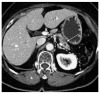

Minimally invasive distal pancreatectomy with splenectomy has been regarded as a safe and effective treatment for benign and borderline malignant pancreatic lesions. However, its application for left-sided pancreatic cancer is still being debated. The clinical evidence for radical antegrade modular pancreatosplenectomy (RAMPS)-based minimally invasive approaches for left-sided pancreatic cancer was reviewed. Potential indications and surgical concepts for minimally invasive RAMPS were suggested. Despite the limited clinical evidence for minimally invasive distal pancreatectomy in left-sided pancreatic cancer, the currently available clinical evidence supports the use of laparoscopic distal pancreatectomy under oncologic principles in well-selected left sided pancreatic cancers. A pancreas-confined tumor with an intact fascia layer between the pancreas and left adrenal gland/kidney positioned more than 1 or 2 cm away from the celiac axis is thought to constitute a good condition for the use of margin-negative minimally invasive RAMPS. The use of minimally invasive (laparoscopic or robotic) anterior RAMPS is feasible and safe for margin-negative resection in well-selected left-sided pancreatic cancer. The oncologic feasibility of the procedure remains to be determined; however, the currently available interim results indicate that even oncologic outcomes will not be inferior to those of open radical distal pancreatosplenectomy.